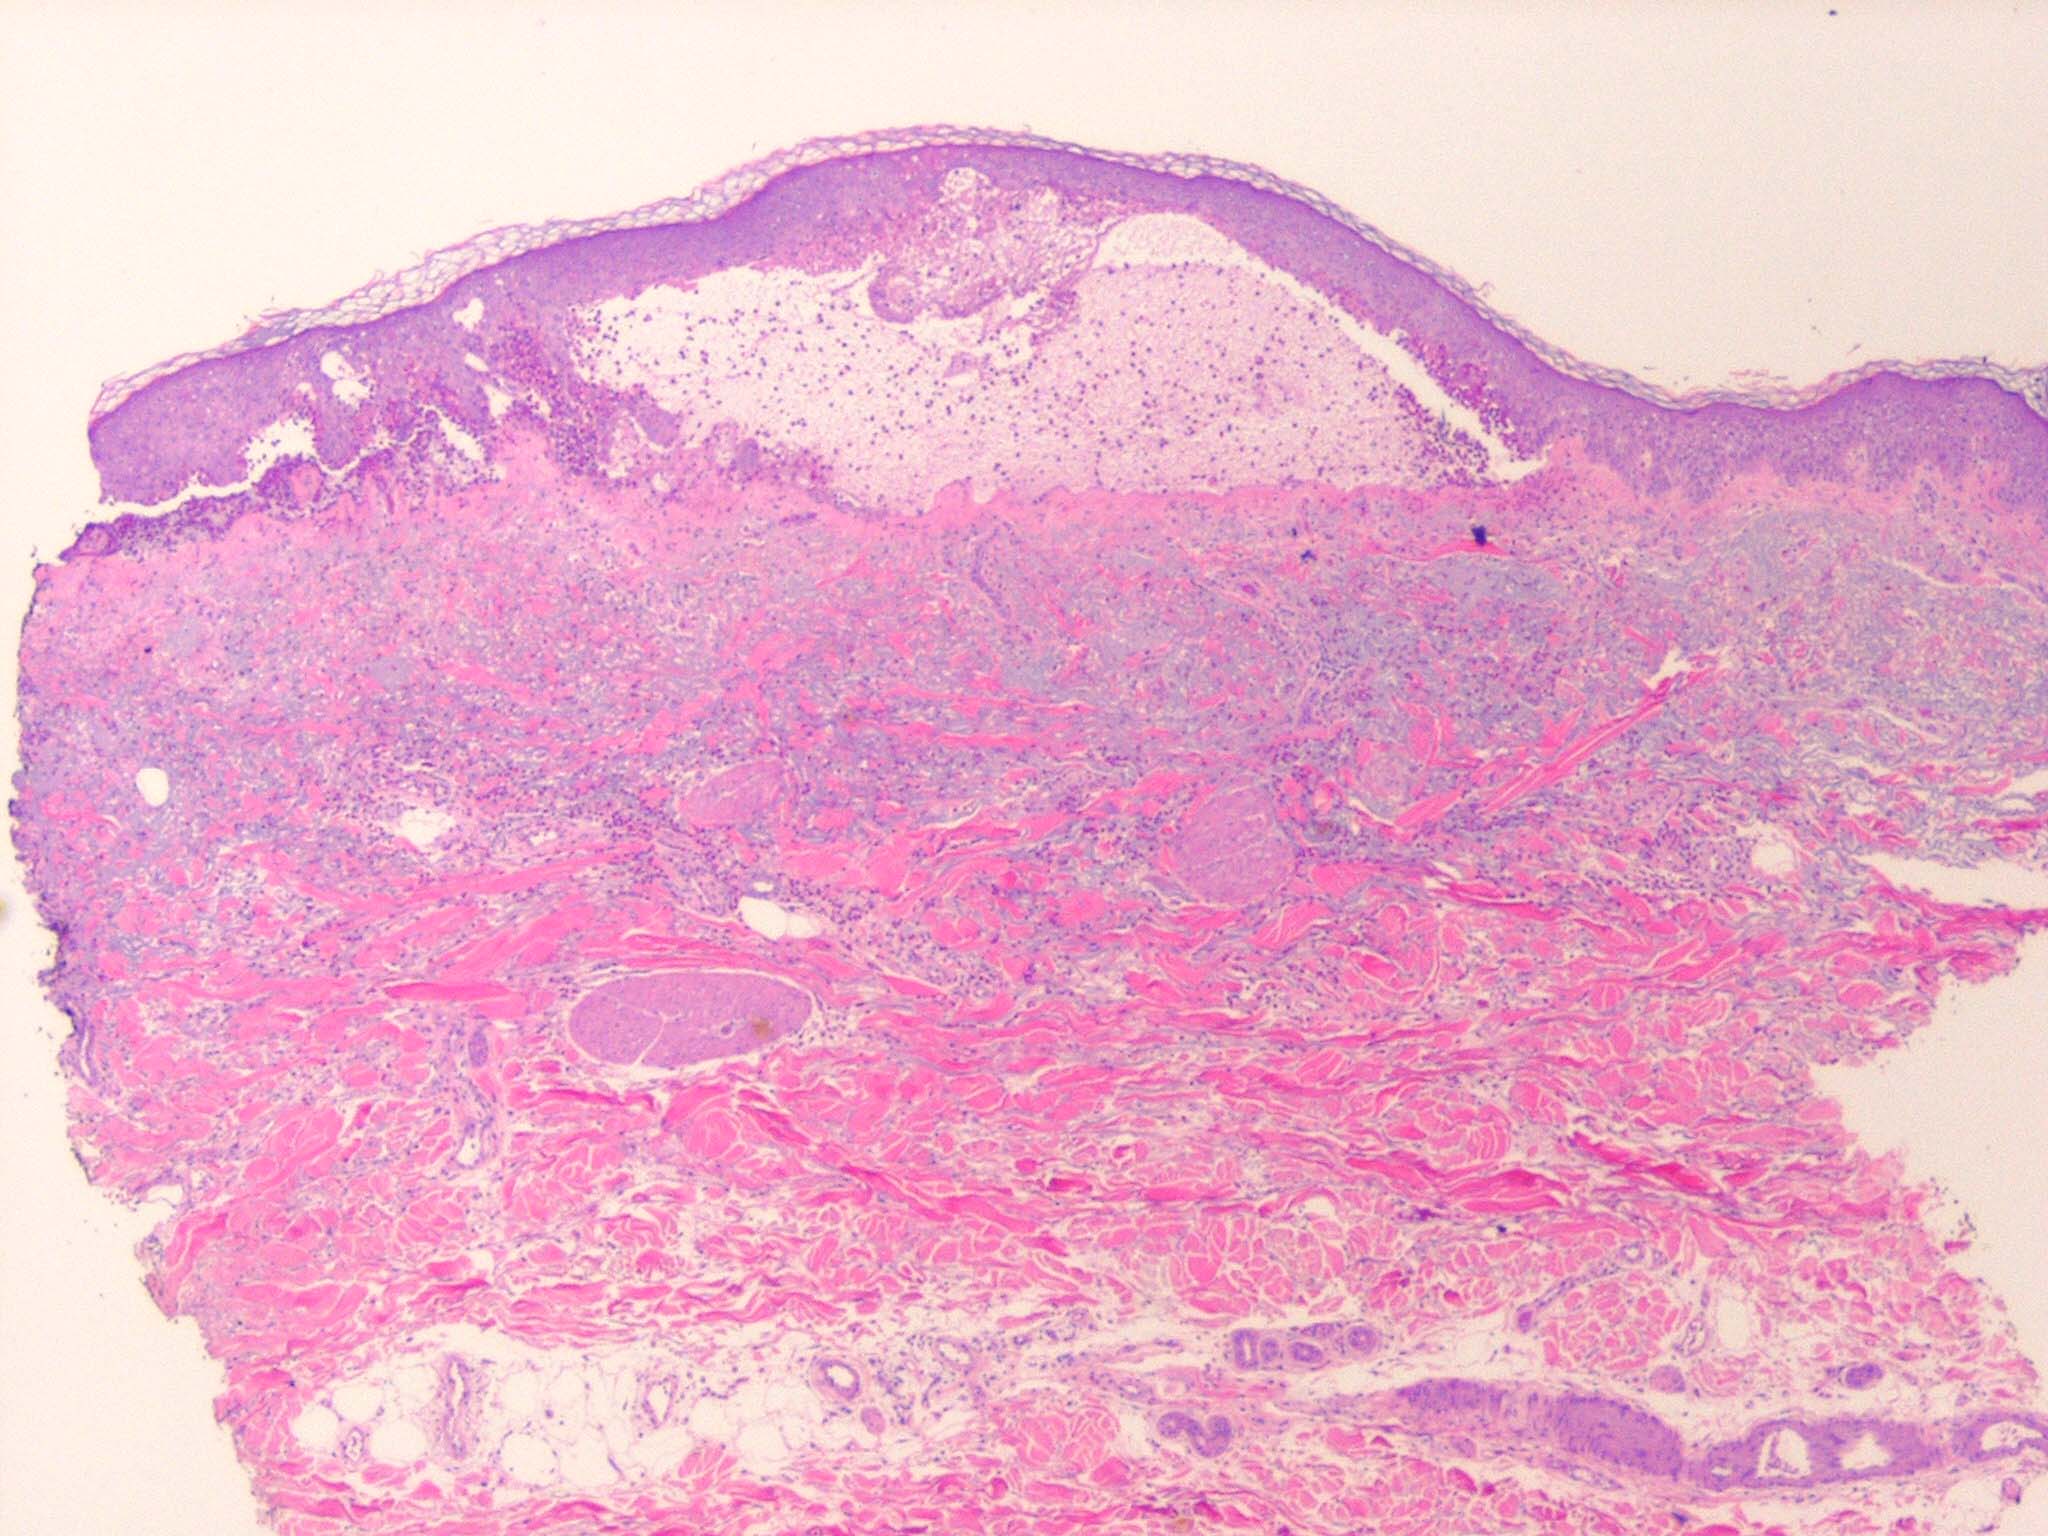

Histopathology.

In early lesions, papillary dermal edema in combination with a cell-poor or cell-rich perivascular lymphocytic and eosinophilic infiltrate is present. The blister arises at the dermal-epidermal junction . In the cell-rich pattern, which correlates clinically with blisters arising on erythematous skin , eosinophilic papillary abscesses may develop with numerous perivascular and interstitial eosinophils intermingled with lymphocytes and neutrophils in the superficial and deep dermis. Early lesions may have the histologic features of eosinophilic cellulitis (Well’s syndrome). Eosinophilic spongiosis may occur. The cell-poor pattem is observed

when blisters develop on relatively normal skin , in which there is usually a scant perivascular lymphocytic infiltrate with few eosinophils, some scattered throughout the dermis and others near the epidermis. The blister contains few inflammatory cells. Epithelial migration and regeneration may result in an intraepidermal split in older blisters. Similar to pemphigus vegetans, a hyperplasia of the epidermis, subepidermal bullae, and accumulations of eosinophils and lymphocytes may be seen.